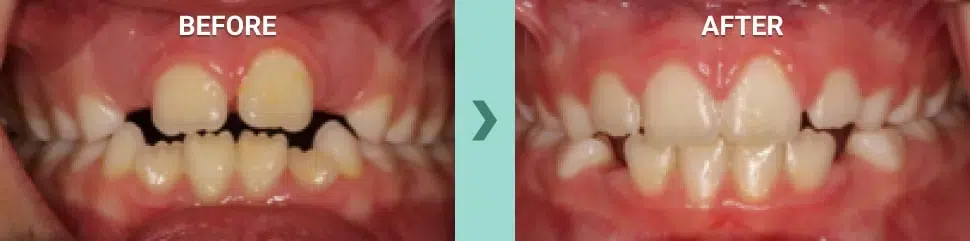

Below is a case successfully treated by Dr. Dan Bruce only using the Myobrace system. This case involved an anterior tongue thrust. The case took 1 year to treat, and we were able to use the habit corrector only due to the lack of considerable crowding, excess overbite, excess underbite or crossbites.

Myobrace® Before and After